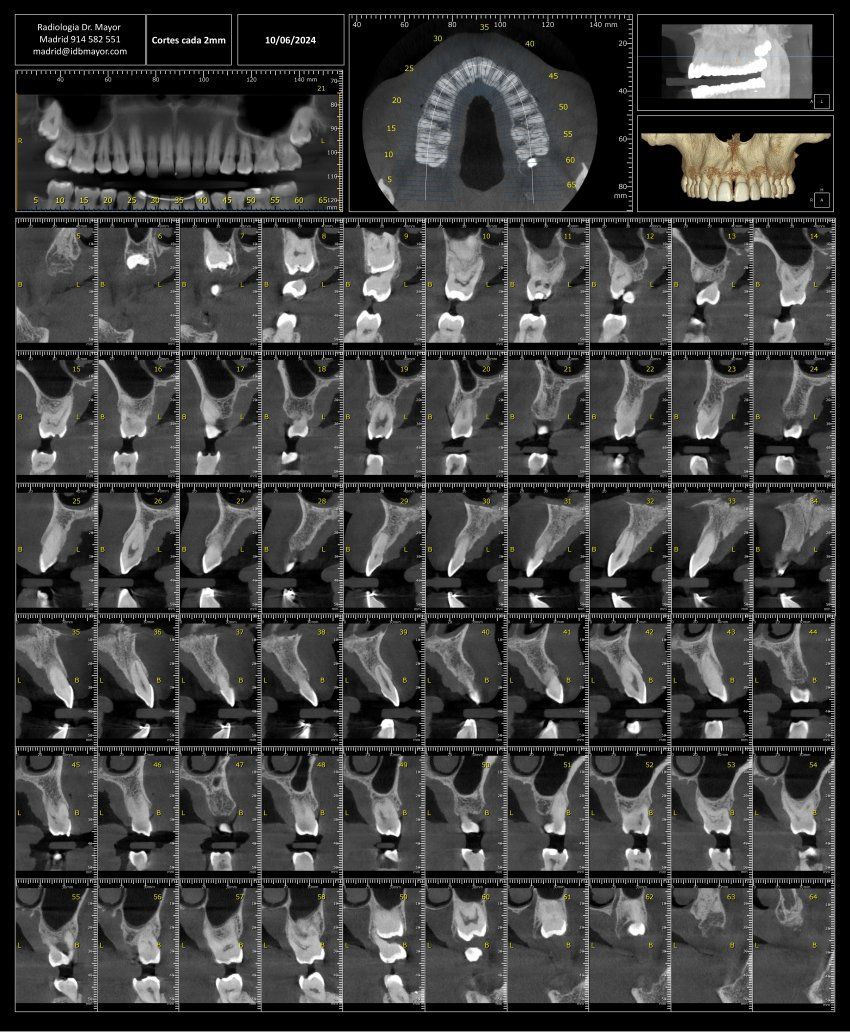

La técnica de diagnóstico por imágenes que se utiliza mediante rayos X, se puede llevar a cabo con diferentes aparatologías. Desde TAC o CBCT a la más clásica radiografía. Sin embargo, la combinación de todas estas imágenes y la tecnología, permite crear modelos 3D.

Mediante un programa (software) los profesionales de la odontología pueden explorar esa combinación de imágenes que generan el modelo 3D de la boca del paciente. Pero, ¿Qué tecnología se utiliza?

En Imagen Diagnóstica Dental Dr. Mayor combinamos el TAC dental o DentaScan 3D y la CBCT. Te contamos más:

TAC dental o DentaScan 3D (Tomografía Axial Computerizada)

Mediante rayos X, permite obtener imágenes en tres dimensiones tanto de los dientes como de los huesos maxilares de los usuarios que se someten a ella.

CBCT de alta resolución o Tomografía Computerizada de Haz Cónica

En este caso, los rayos X se emiten de una forma cónica, realizando un escáner intraoral, y mediante rotación de 360º lo que permite obtener imágenes en 3D. Es muy útil para poder identificar complicaciones médicas y evaluar la mandíbula de los pacientes.